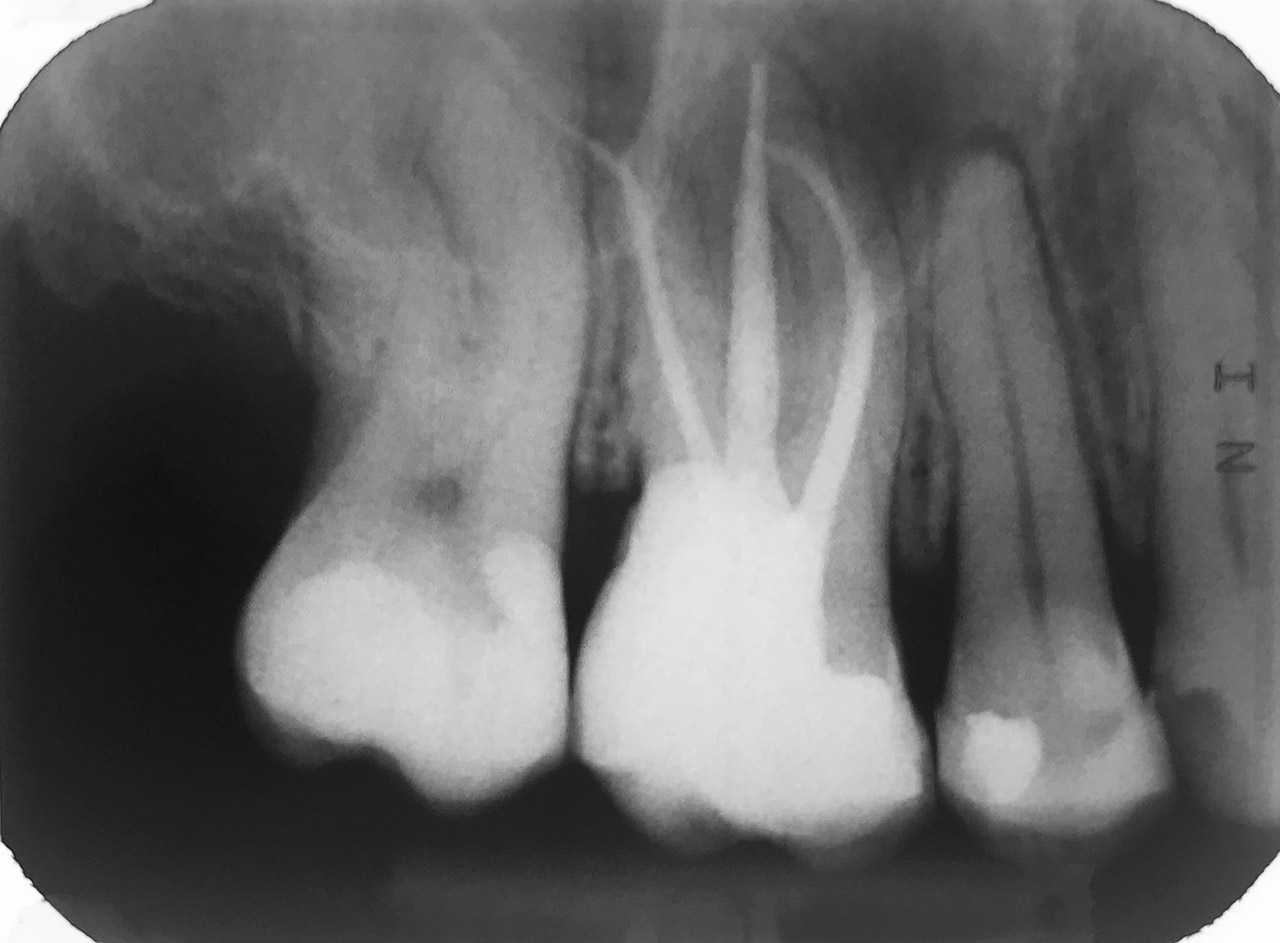

Endodontie/Wurzelbehandlung:

Befund: Aufbißschmerz und Schwellung auf Zahn 46. Frisch zementierte Krone (alio loco).

Therapie: Abnahme der Krone, Entfernung der Zementreste, Revision der insuffizienten Wurzelbehandlung.

Glasfaserstifte und neue Krone, beides adhäsiv zementiert.